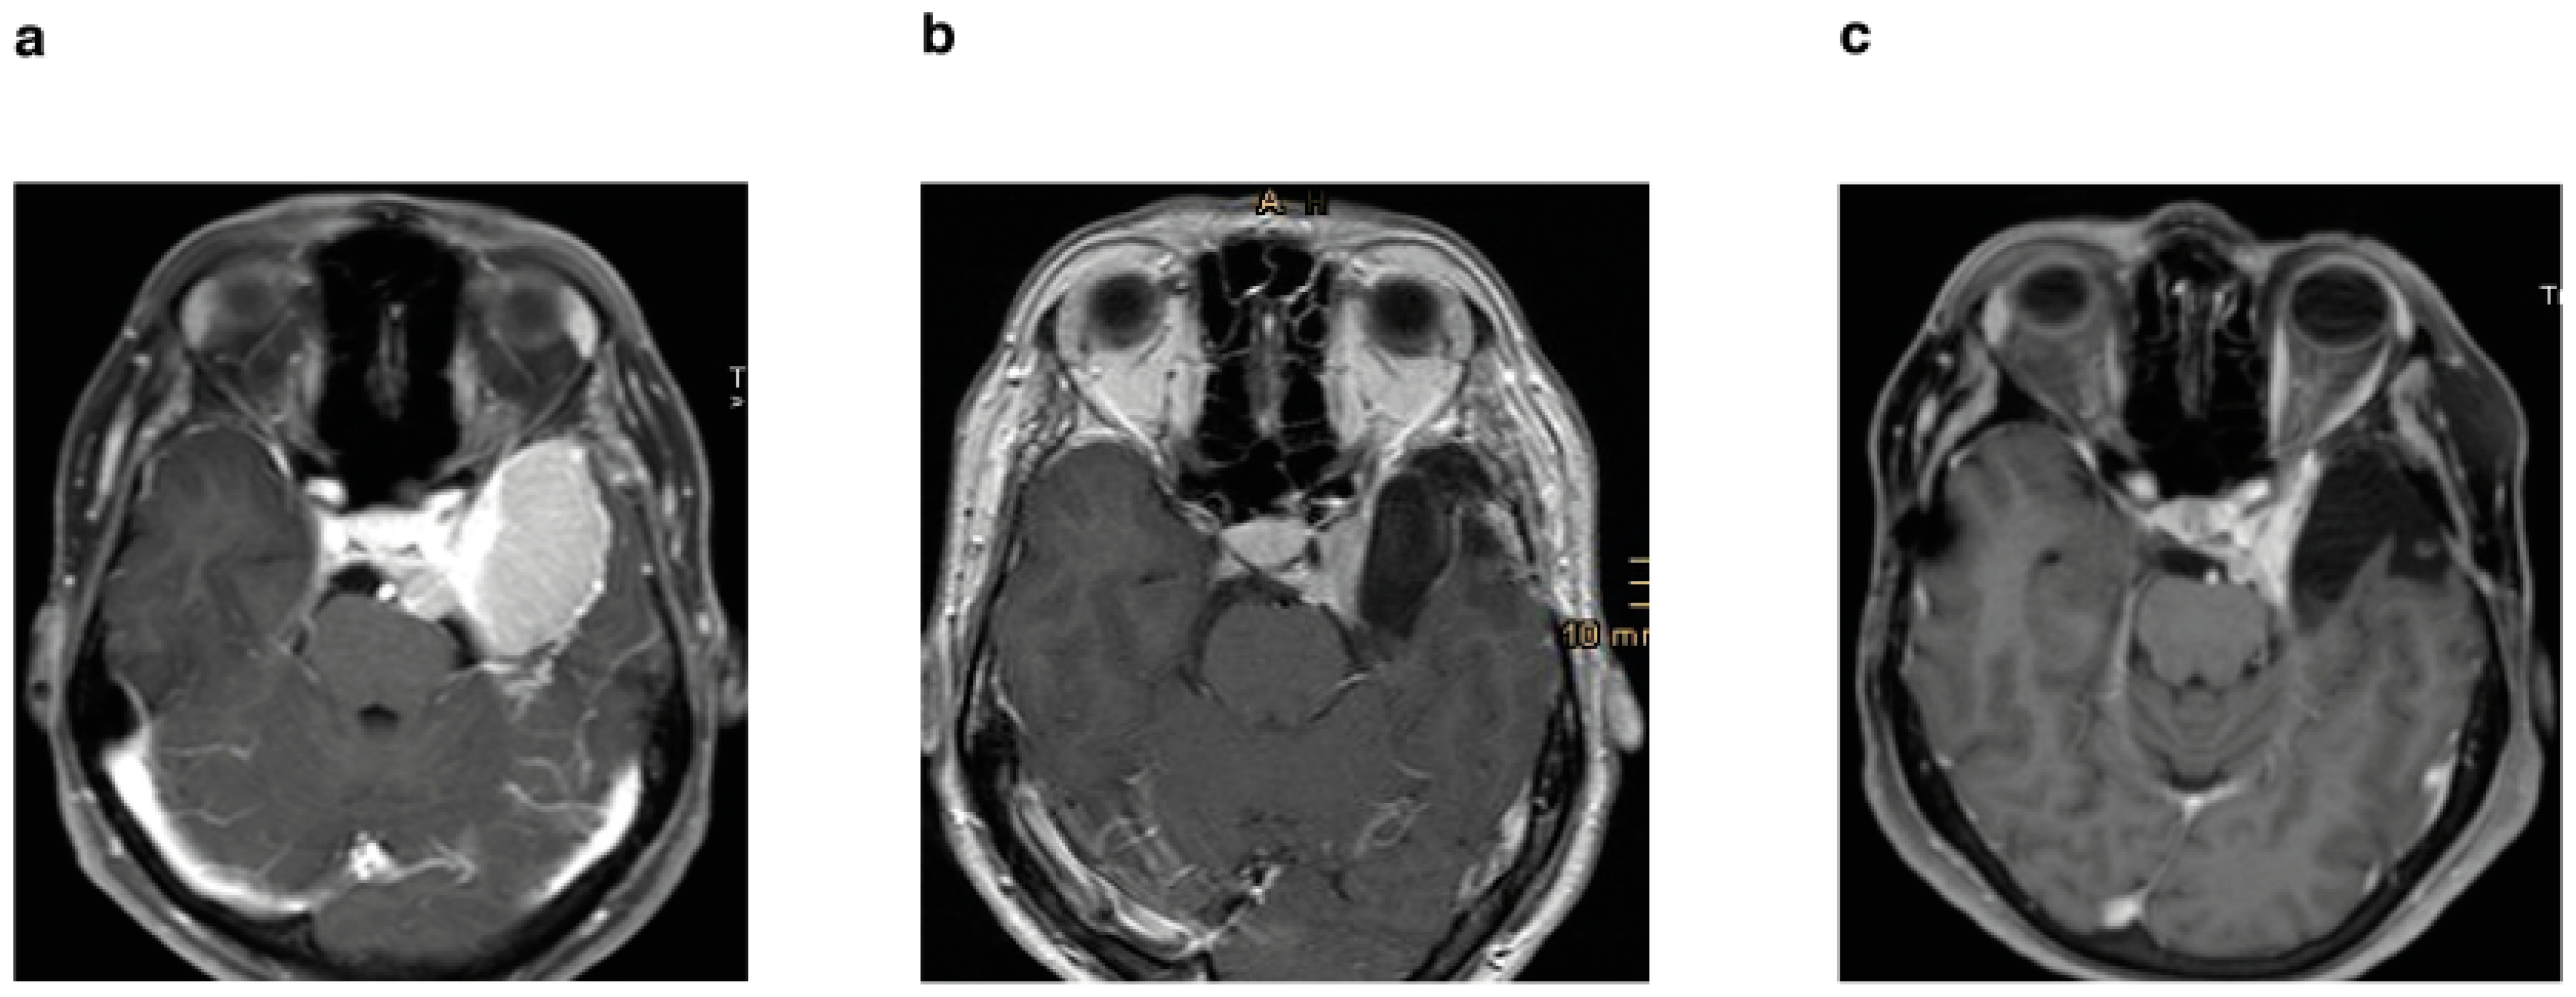

Figure 5. (a) Preoperative axial T1-weighted sequence with gadolinium enhancement of a patient who underwent STR and postoperative stereotactic radiotherapy; (b) postoperative MRI after 3 months; (c) follow-up MRI after 11 years without progression.

3.2. Postoperative Adjuvant Radiotherapy in WHO Grade I Meningioma

Thirty-five patients (37%) were treated postoperatively with stereotactic radiotherapy of the residual tumor in the cavernous sinus (Figure 4a), of which three patients had tumor recurrence/progression (3.1%). In contrast, 60 patients (63%) underwent surgery alone, of which 24 patients (25.2%) had tumor recurrence/progression. Both the Kaplan–Meier analysis (p = 0.0002) (Figure 4b) and the univariate (p = 0.0032) and multivariate analysis (p ≤ 0.0001) showed significant differences for the two groups (Figure 5) (Table 2).

In our study, Kaplan–Meier analysis showed prolonged PFS in patients who received adjuvant radiotherapy (Figure 4b), as did the additional multivariate analysis that showed significantly better PFS (Table 2). These results are in line with other studies [11,13,14,15,27]. The meta-analysis performed by Sughrue et al. (2010a) showed the superiority of radiation treatment over surgical resection in terms of preserving cranial nerve function in cavernous sinus meningioma. Nevertheless, they emphasized the importance of long-term follow-up after radiotherapy due to the potential for aggressive growth [11]. There is strong evidence for the primarily use of stereotactic radiotherapy in meningiomas invading the cavernous sinus. However, this is limited by the size of the tumor, its extracavernous extent, and the proximity to radiosensitive vital nerve tissue. In addition, cavernous sinus meningiomas and sphenoid wing meningiomas are two types of tumors that differ in their origin, behavior, and clinical manifestation. In most cases, sphenoid wing meningiomas become clinically apparent after they reach a certain size and infiltrate the cavernous sinus. Therefore, many authors recommend surgical decompression first to reduce the proximity of these lesions to the optic nerve, diencephalon, and brainstem, followed by radiotherapy to reduce morbidity [11,14,15].